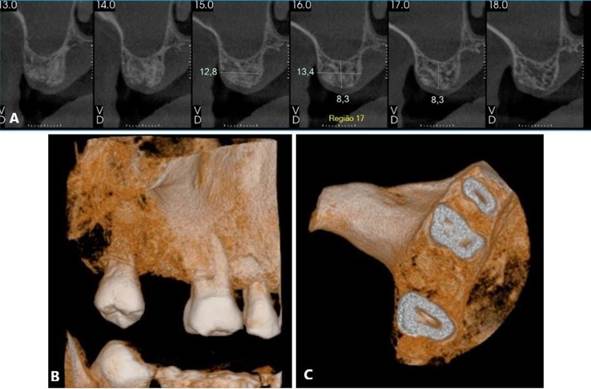

Inicialmente, o procedimento cirúrgico consistiu pela remoção dos implantes dentários (Figura 04. B), realização de enxerto imediato (Bio-Oss, Geistlinch, Wolhusen – Suíça), através da técnica de reconstrução tipo tenda, e uso da membrana de colágeno (Bio-Gide, Geistlinch, Wolhusen – Suíça). O Quadro 1 apresenta as principais medidas para avaliação do posicionamento do implante. Após 6 meses, foram instalados dois implantes dentários extra curtos ARCSYS (FGM, Joinvile – SC, Brasil) 4,0 mm x 6,0 mm x 5,0 mm do lado direito e dois implantes na região esquerda 5,0 mm x 5,0 mm. As figuras 05 e 06 evidenciam aspecto radiográfico após a etapa inicial. As recomendações pós-operatórias e a prescrição medicamentosa foram realizadas, resultando em ausência de complicações após a intervenção. O acompanhamento foi feito durante 5 anos, com resultado satisfatório (Figura 7. A – E).

Figura 05. Exames de imagem da região inferior direita. A) Vista panorâmica. B) Reconstruções tridimensionais. C) Cortes transversais oblíquos.

Figura 06. Exames de imagem da região inferior esquerda. A) Vista panorâmica. B) Reconstruções tridimensionais. C) Cortes transversais oblíquos.